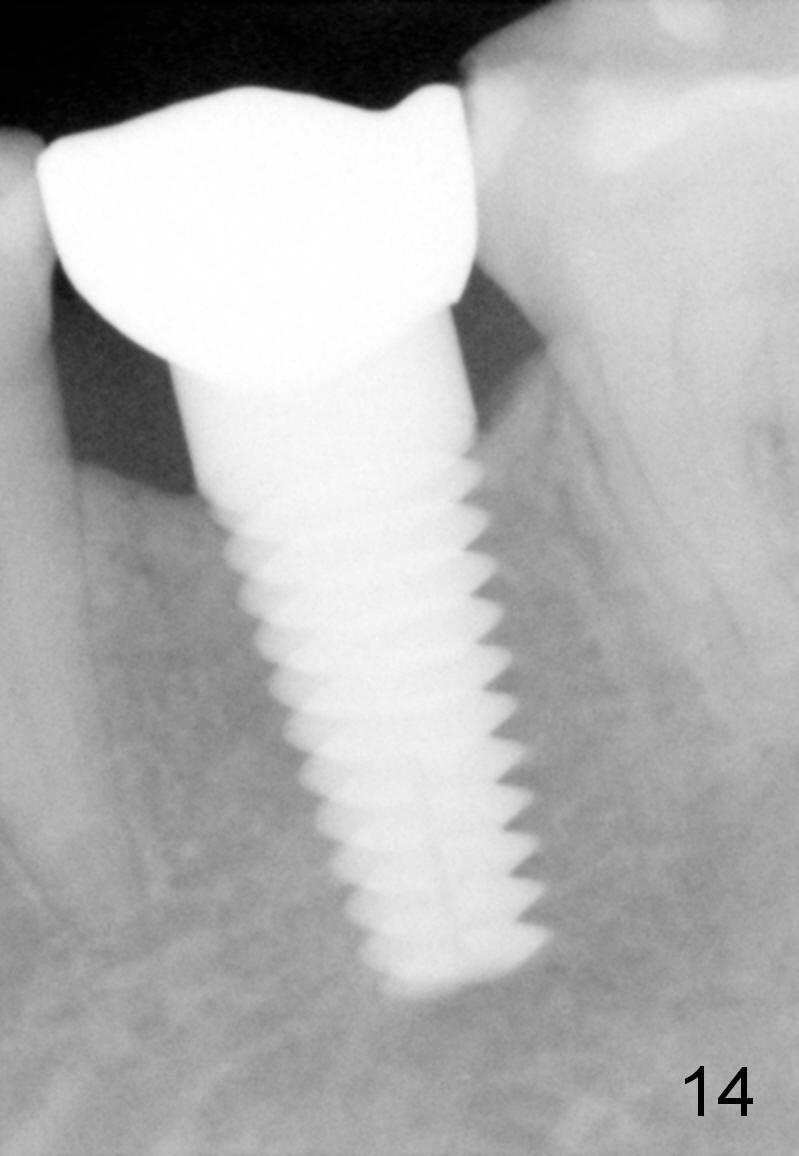

Eleven months post bonding (17 months postop), there is cortical bone formation at the mesial and distal crests (Fig.14).  It remains the same 1 year 10 months post bonding (Fig.15).  There is no bone loss 3 years 5 months post cementation (Fig.16).  In fact the crestal cortical bone thickens.